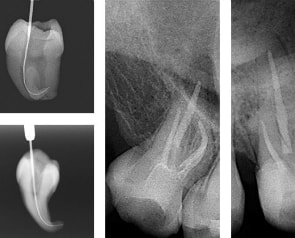

根管長測定器及び、根管治療器

歯の中には「歯髄」と呼ばれる神経や血管を含む組織があります。

むし歯や外傷によって歯髄が感染したり壊死したりしてしまうと、歯髄を取り除く根管治療が必要になります。

根管治療には細心の注意をはらいながら行います。

現在は素晴らしい機器が誕生し数年後に再治療が必要になる等のリスクも低減できています。

この機器は根管長を確実に把握し、神経を正確に洗浄・拡大するなど適切な歯随の治療を行う機器です。

確実性がアップし治療時間も早くすみます。

根幹充填

より完璧な根管治療のために。

残念ながら神経を取るに至る治療となってしまった場合、神経部分に充填するガッタパーチャをより完璧に充填するための機器です。

根管の中に隙間があると、そこから菌が繁殖して、神経を取った歯でも膿がたまって治療のやり直しになります。

また、根管の中に神経の通っている繊維が沢山あります。

その細かく分岐しているところまでガッタパーチャで根充し、より緊密にするのが目的です。

そうすることによって、歯の根に空洞を作らず、菌の繁殖の元となるすかすかな場所まで密閉するという役割があります。